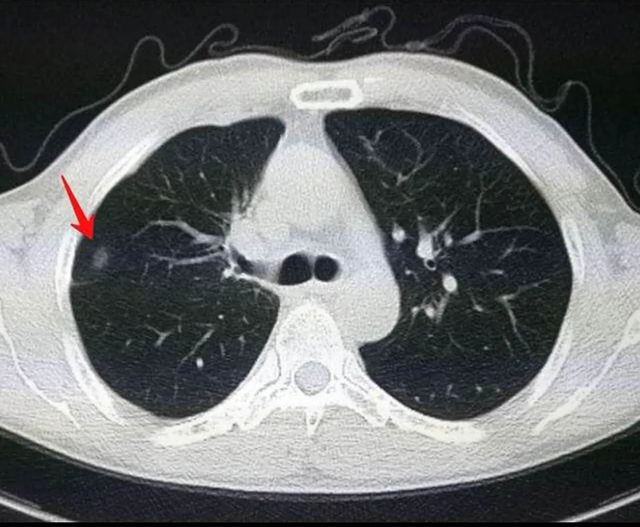

所謂肺部結(jié)節(jié),即醫(yī)學(xué)上所說的孤立性肺結(jié)節(jié)。孤立性肺結(jié)節(jié)指的是單一的、邊界清楚的、影像不透明的、直徑≤30 mm、周圍為含氣肺組織所包繞的病變,沒有肺不張、肺門增大或胸腔積液表現(xiàn)。對于直徑>30 mm,我們常稱之為腫塊的情況,惡性的概率就非常高了。

從CT上看,肺部結(jié)節(jié)分為實性結(jié)節(jié)、非實性結(jié)節(jié)(如磨玻璃結(jié)節(jié)、混合結(jié)節(jié))。肺結(jié)節(jié)有良性和惡性之分。一般來講,結(jié)節(jié)越小惡性的可能性越低,據(jù)報道直徑大于2厘米的肺部結(jié)節(jié)約40%是惡性的,小于0.8 厘米的肺部小結(jié)節(jié)約90%以上為良性。